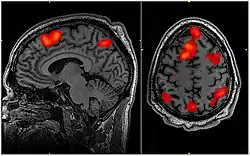

A audiologia é um ramo da ciência que estuda a audição, seu equilíbrio e distúrbios relacionados. Os profissionais com formação em fonoaudiologia, que tratam pessoas com perda auditiva e, de forma proativa, evitam possíveis danos a audição. O Audiologista é o fonoaudiólogo especialista que se dedica ao estudo do sentido audição, desde a recepção das ondas sonoras pelo ouvido até o completo processamento das informações auditivas pelo córtex do sistema nervoso central, dedicando-se ao estudo da anatomia, da fisiologia, da neurofisiologia e das patologias de todo o aparelho auditivo.[5] Este profissional sem dúvida, é o mais capacitado para diagnosticar, atestar e tratar os distúrbios da audição e suas consequências no dia-a-dia do indivíduo por eles acometido, daí o porquê vem sendo muito requisitado na esfera do poder judiciário para que realize perícias nas questões que envolvem a audição, pois, para o judiciário não basta saber que há lesão e o seu grau, é fundamental para a decisão do Juiz saber de que forma aquela lesão afeta a vida do cidadão.[6]

O Audiologista é por vezes confundido com o Otorrinolaringologista, que é o especialista que se dedica ao estudo do ouvido, não tendo seu espectro de estudo ampliado para todos os aspectos do sentido da audição, seu processamento e suas influências no processo de linguagem e comunicação humana. O Audiologista realiza exames audiológicos e otoneurológicos -audiometria tonal limiar(via aérea e óssea), logoaudiometria(limiar de reconhecimento de fala, limiar de detecção de fala, índice de reconhecimento de fala e índice porcentual de reconhecimento de fala), audiometria vocal, imitânciometria acústica, provas de função tubária, teste de reflexos neurológicos estapedianos, emissões otoacústicas transientes e evocadas por produto de distorção, audiometria de tronco encefálico, potenciais evocados de curta, média e de longa latência, monitoração transoperatória em neurocirurgias, vídeonistagmografia comum e infravermelha, vectoeletronistagmografia, rinometria acústica, exames de processamento auditivo central (avaliação de como o sistema nervoso central está processando a audição, dentre outros) para verificar se a função auditiva dos pacientes está dentro do padrão normal ou se apresenta algum tipo de alteração.

Acompanha o desenvolvimento do bebê desde o nascimento, e a partir daí em consultas regulares, nos aspectos relacionados ao processo de aquisição e desenvolvimento da linguagem. Estuda problemas relacionados com a aquisição e o desenvolvimento da linguagem, faz diagnósticos de atrasos ou alterações de linguagem, estabelece o tratamento para a habilitação dessas crianças. Faz avaliação, diagnóstico, prognósticos e estabelece tratamentos para pacientes que adquiriram a linguagem mas a perderam ou passam a apresentar algum distúrbio ou anormalidade por algum motivo, a exemplo de quem sofreu derrame cerebral também chamado de AVE (acidente vascular encefálico), traumas cranianos, isquemias cerebrais, doenças degenerativas do sistema nervoso central (esclerose múltipla, mal de Alzheimer, degeneração olivopontocerebelar, mal de Parkinson, etc.), tumores intracranianos, sequelas de neurocirurgias e outras condições clínicas. Essas dificuldades na aquisição da linguagem, interferem também no desenvolvimento da escrita.[8]